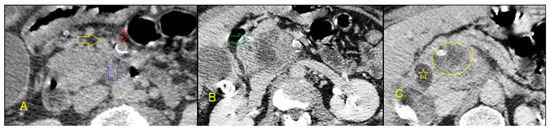

6.3. Endoscopic Ultrasound-Guided Fine-Needle Aspiration

6.4. Endoscopic Ultrasound-Guided Fine-Needle Biopsy

- Wang, W.; Shpaner, A.; Krishna, S.G.; Ross, W.A.; Bhutani, M.S.; Tamm, E.P.; Raju, G.S.; Xiao, L.; Wolff, R.A.; Fleming, J.B. Use of EUS-FNA in diagnosing pancreatic neoplasm without a definitive mass on CT. Gastrointest. Endosc. 2013, 78, 73–80. [Google Scholar] [CrossRef] [PubMed]

- De Moura, D.T.H.; De Moura, E.G.H.; Bernardo, W.M.; De Moura, E.T.H.; Baracat, F.I.; Kondo, A.; Matuguma, S.E.; Artifon, E.L.A. Endoscopic retrograde cholangiopancreatography versus endoscopic ultrasound for tissue diagnosis of malignant biliary stricture: Systematic review and meta-analysis. Endosc. Ultrasound 2018, 7, 10. [Google Scholar] [CrossRef]

- Ayres, L.R.; Kmiotek, E.K.; Lam, E.; Telford, J.J. A comparison of endoscopic ultrasound-guided fine-needle aspiration and fine-needle biopsy in the diagnosis of solid pancreatic lesions. Can. J. Gastroenterol. Hepatol. 2018, 2018, 1–6. [Google Scholar] [CrossRef]

- Van Riet, P.A.; Larghi, A.; Attili, F.; Rindi, G.; Nguyen, N.Q.; Ruszkiewicz, A.; Kitano, M.; Chikugo, T.; Aslanian, H.; Farrell, J. A multicenter randomized trial comparing a 25-gauge EUS fine-needle aspiration device with a 20-gauge EUS fine-needle biopsy device. Gastrointest. Endosc. 2019, 89, 329–339. [Google Scholar] [CrossRef]

- Asokkumar, R.; Ka, C.Y.; Loh, T.; Ling, L.K.; San, T.G.; Ying, H.; Tan, D.; Khor, C.; Lim, T.; Soetikno, R. Comparison of tissue and molecular yield between fine-needle biopsy (FNB) and fine-needle aspiration (FNA): A randomized study. Endosc. Int. Open 2019, 7, E955–E963. [Google Scholar] [CrossRef]

- Facciorusso, A.; Bajwa, H.S.; Menon, K.; Buccino, V.R.; Muscatiello, N. Comparison between 22G aspiration and 22G biopsy needles for EUS-guided sampling of pancreatic lesions: A meta-analysis. Endosc Ultrasound. 2019, 10. [Google Scholar] [CrossRef]

- Khan, M.A.; Grimm, I.S.; Ali, B.; Nollan, R.; Tombazzi, C.; Ismail, M.K.; Baron, T.H. A meta-analysis of endoscopic ultrasound–fine-needle aspiration compared to endoscopic ultrasound–fine-needle biopsy: Diagnostic yield and the value of onsite cytopathological assessment. Endosc. Int. Open 2017, 5, E363–E375. [Google Scholar] [CrossRef]